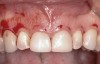

Following anesthesia, a scalloped incision was made on the keratinized tissue (Figure 3). In the interproximal area, a papilla-sparing incision was made. A full-thickness flap was raised to give access to the underlying bone (Figure 4). Both osteoplasty and ostectomy were performed to position the bone crest approximately 2 mm to 3 mm from the CEJ (Figure 5). The gingival tissue was repositioned, coinciding with the initial labial incision and the interproximal papilla. Interrupted sutures were placed (Figure 6), which were removed 7 days following the surgery.

Fig 4. Flap elevation pre-osseous resection.

Figure 4